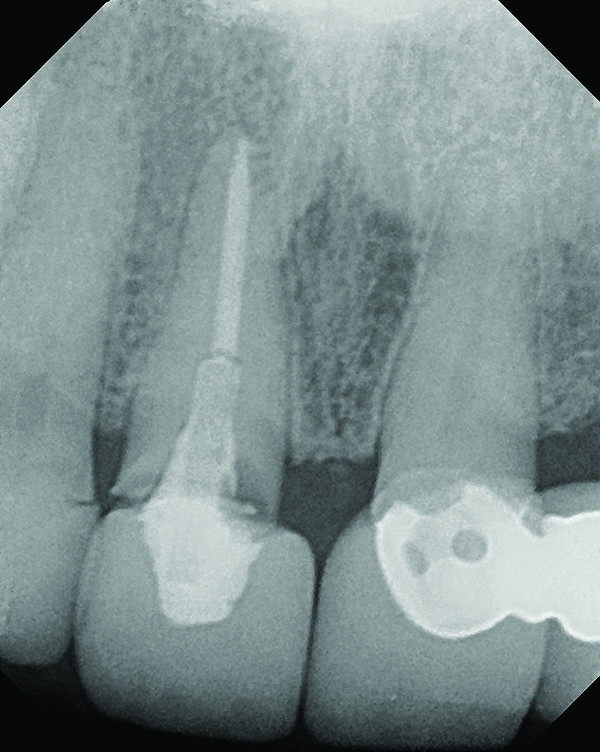

A 63-year-old female patient presented with mobility of her right maxillary incisor, tooth No. 8, secondary to endodontic therapy (Figure 1). Her medical and dental histories were non-contributory. Clinical and radiographic evaluations revealed an 8-mm probing depth on the palatal aspect. The tooth was deemed to be fractured (Figure 2). The treatment plan accepted by the patient was for extraction, immediate implant placement, and immediate provisional restoration, if possible.

Fig 2. Periapical radiograph revealing the fractured central incisor.

Figure 2